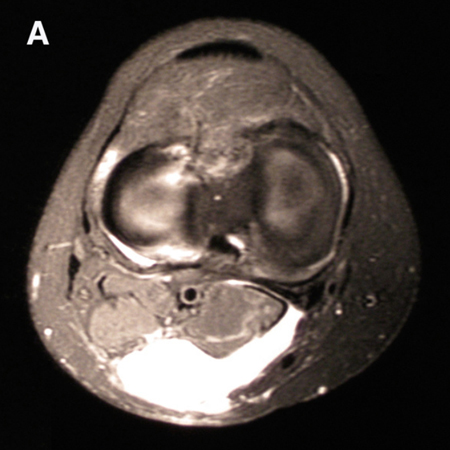

O corno posterior do menisco medial é a única estrutura de reforço nesse local. A degeneração do menisco medial, junto com as condições em que a pressão intra-articular aumenta, faz a cápsula fraca formar uma protuberância, dando origem a um cisto poplíteo na fossa poplítea póstero-medial.[1][Figure caption and citation for the preceding image starts]: Ressonância nuclear magnética (RNM) pré-operatória ponderada em T2 mostrando coleção de fluidos posterior em comunicação com a articulação medial posterior em um paciente com um cisto poplíteo secundário à sinovite vilonodular pigmentadaAdaptado de Tosti R, Kelly JD 4th. A sinovite vilonodular pigmentada apresentando-se como um cisto de Baker. Am J Orthop (Belle Mead NJ). 2011;40:528-531; usado com permissão [Citation ends].